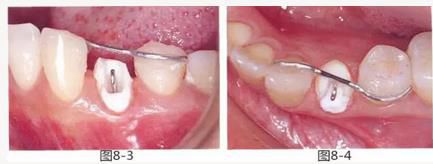

圖8-3 使用方絲和鏈狀橡皮圈,通過正畸的手段挺出牙齒。

圖8-4 使用粘接性樹脂,將S狀方絲固定在鄰牙上。